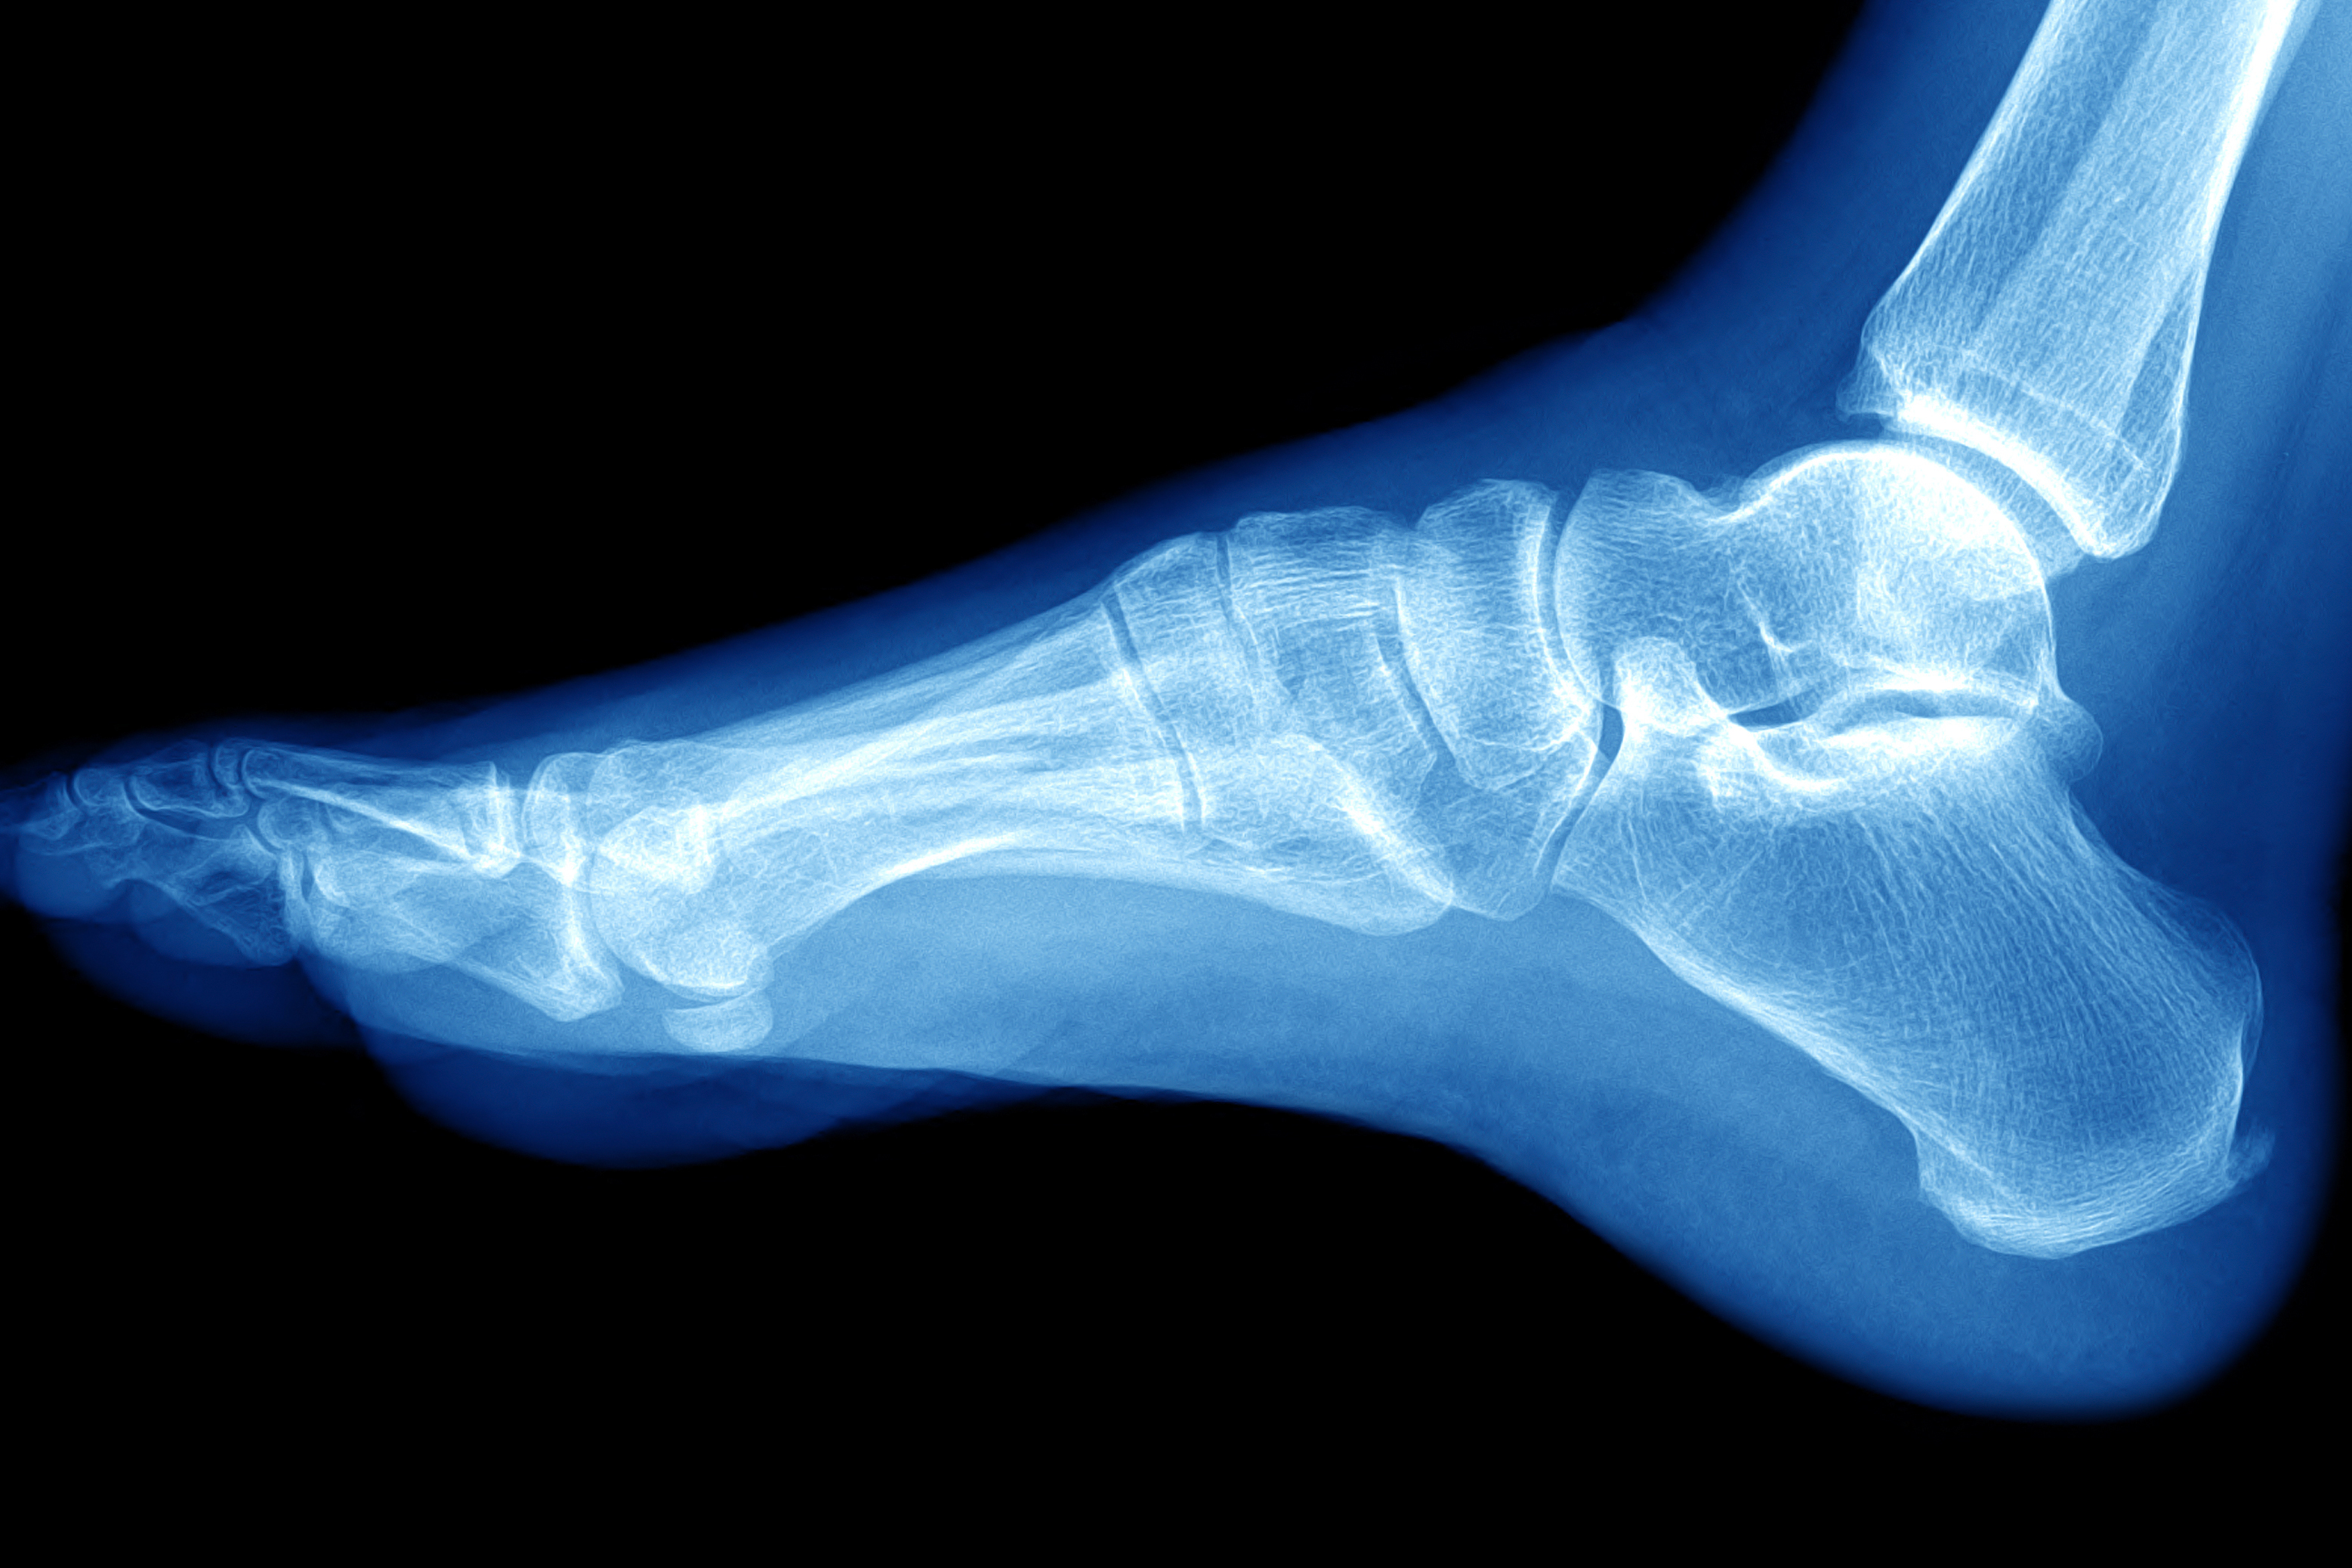

Здоровье на первом месте: диагностика и лечение через рентгеноскопию конечностей

Раздел: Снимки-откровения